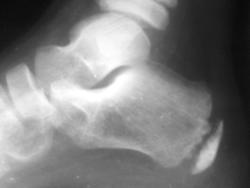

Ребенок М.11лет жалуется на боли в пятках, в конце дня, травмы не было

Все-таки остеохондропатия апофиза пяточной кости, явление достаточное редкое. Чаще имеет место банальная перегрузка, при сопутствующей ортопедической патологии. Согласен надо доснять другую стопу.

Рентгенография обязательна, но не для подтверждения диагноза, а скорее для исключения других причин боли в пятке. Часто обнаруживаемая неровность пяточного росткового хряща не обязательно свидетельствует об остеохондропатии бугра пяточной кости. Еще не помешало бы увидеть, кроме «шероховатости» бугра пяточной кости, уплотнение и фрагментацию апофиза.